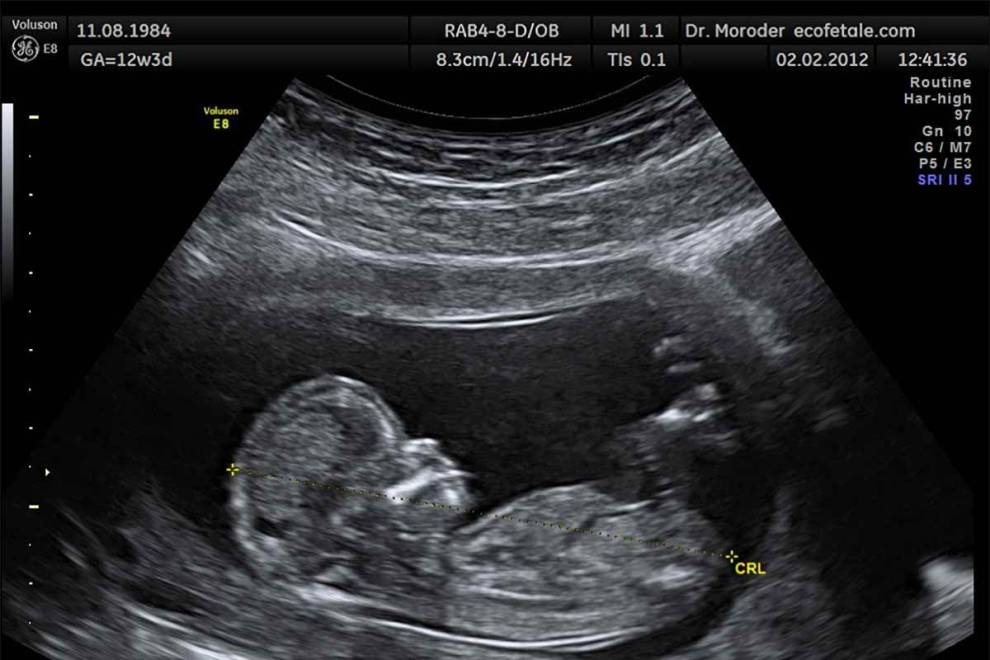

#19 - The Ramzi Method

This one is a lot of fun, and involves looking at your baby's first ultrasound.

It's based on basically non-existent science, but it's a fun method.

We describe the Ramzi Method in full here!